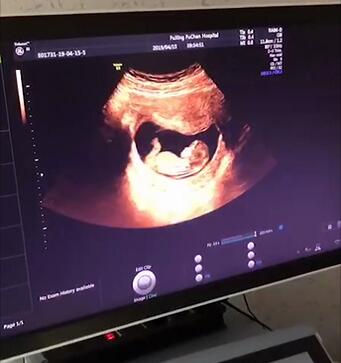

3.大排畸

大排畸一般是在孕22~28周进行检查。孕妇一般都对四维彩超比较期待,因为可以较为清晰地看到宝宝的样子。